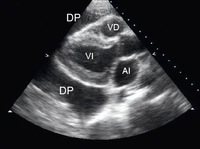

Evaluación del derrame pericárdico

Vista apical de 4 cámaras de un ecocardiograma 2-dimensional de un paciente con derrame pericárdico tuberculoso; AI = aurícula izquierda, VI = ventrículo izquierdo, Derr. per.= derrame pericárdico; AD = aurícula derecha, VD = ventrículo derecho

De: George S, Salama AL, Uthaman B, et al. Heart. 2004; 90:1338-1339